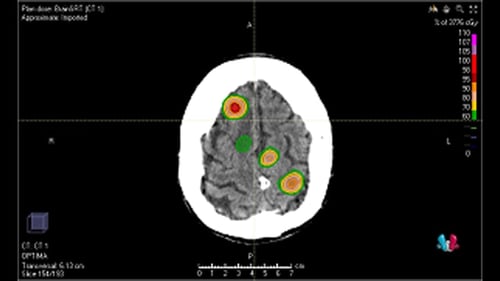

・転移性脳腫瘍

転移性脳腫瘍は腫瘍サイズが大きく症状が強い場合などを除いては手術となることは少なく、放射線治療を行うことが多いです。転移の数が少ない場合には、病変部位に照射範囲を絞って高線量を当てて治療を行う脳定位放射線治療が有効です。脳定位放射線治療は3~5回の治療となります。副作用はてんかん、放射線脳壊死などがあります。(図:脳定位放射線治療)